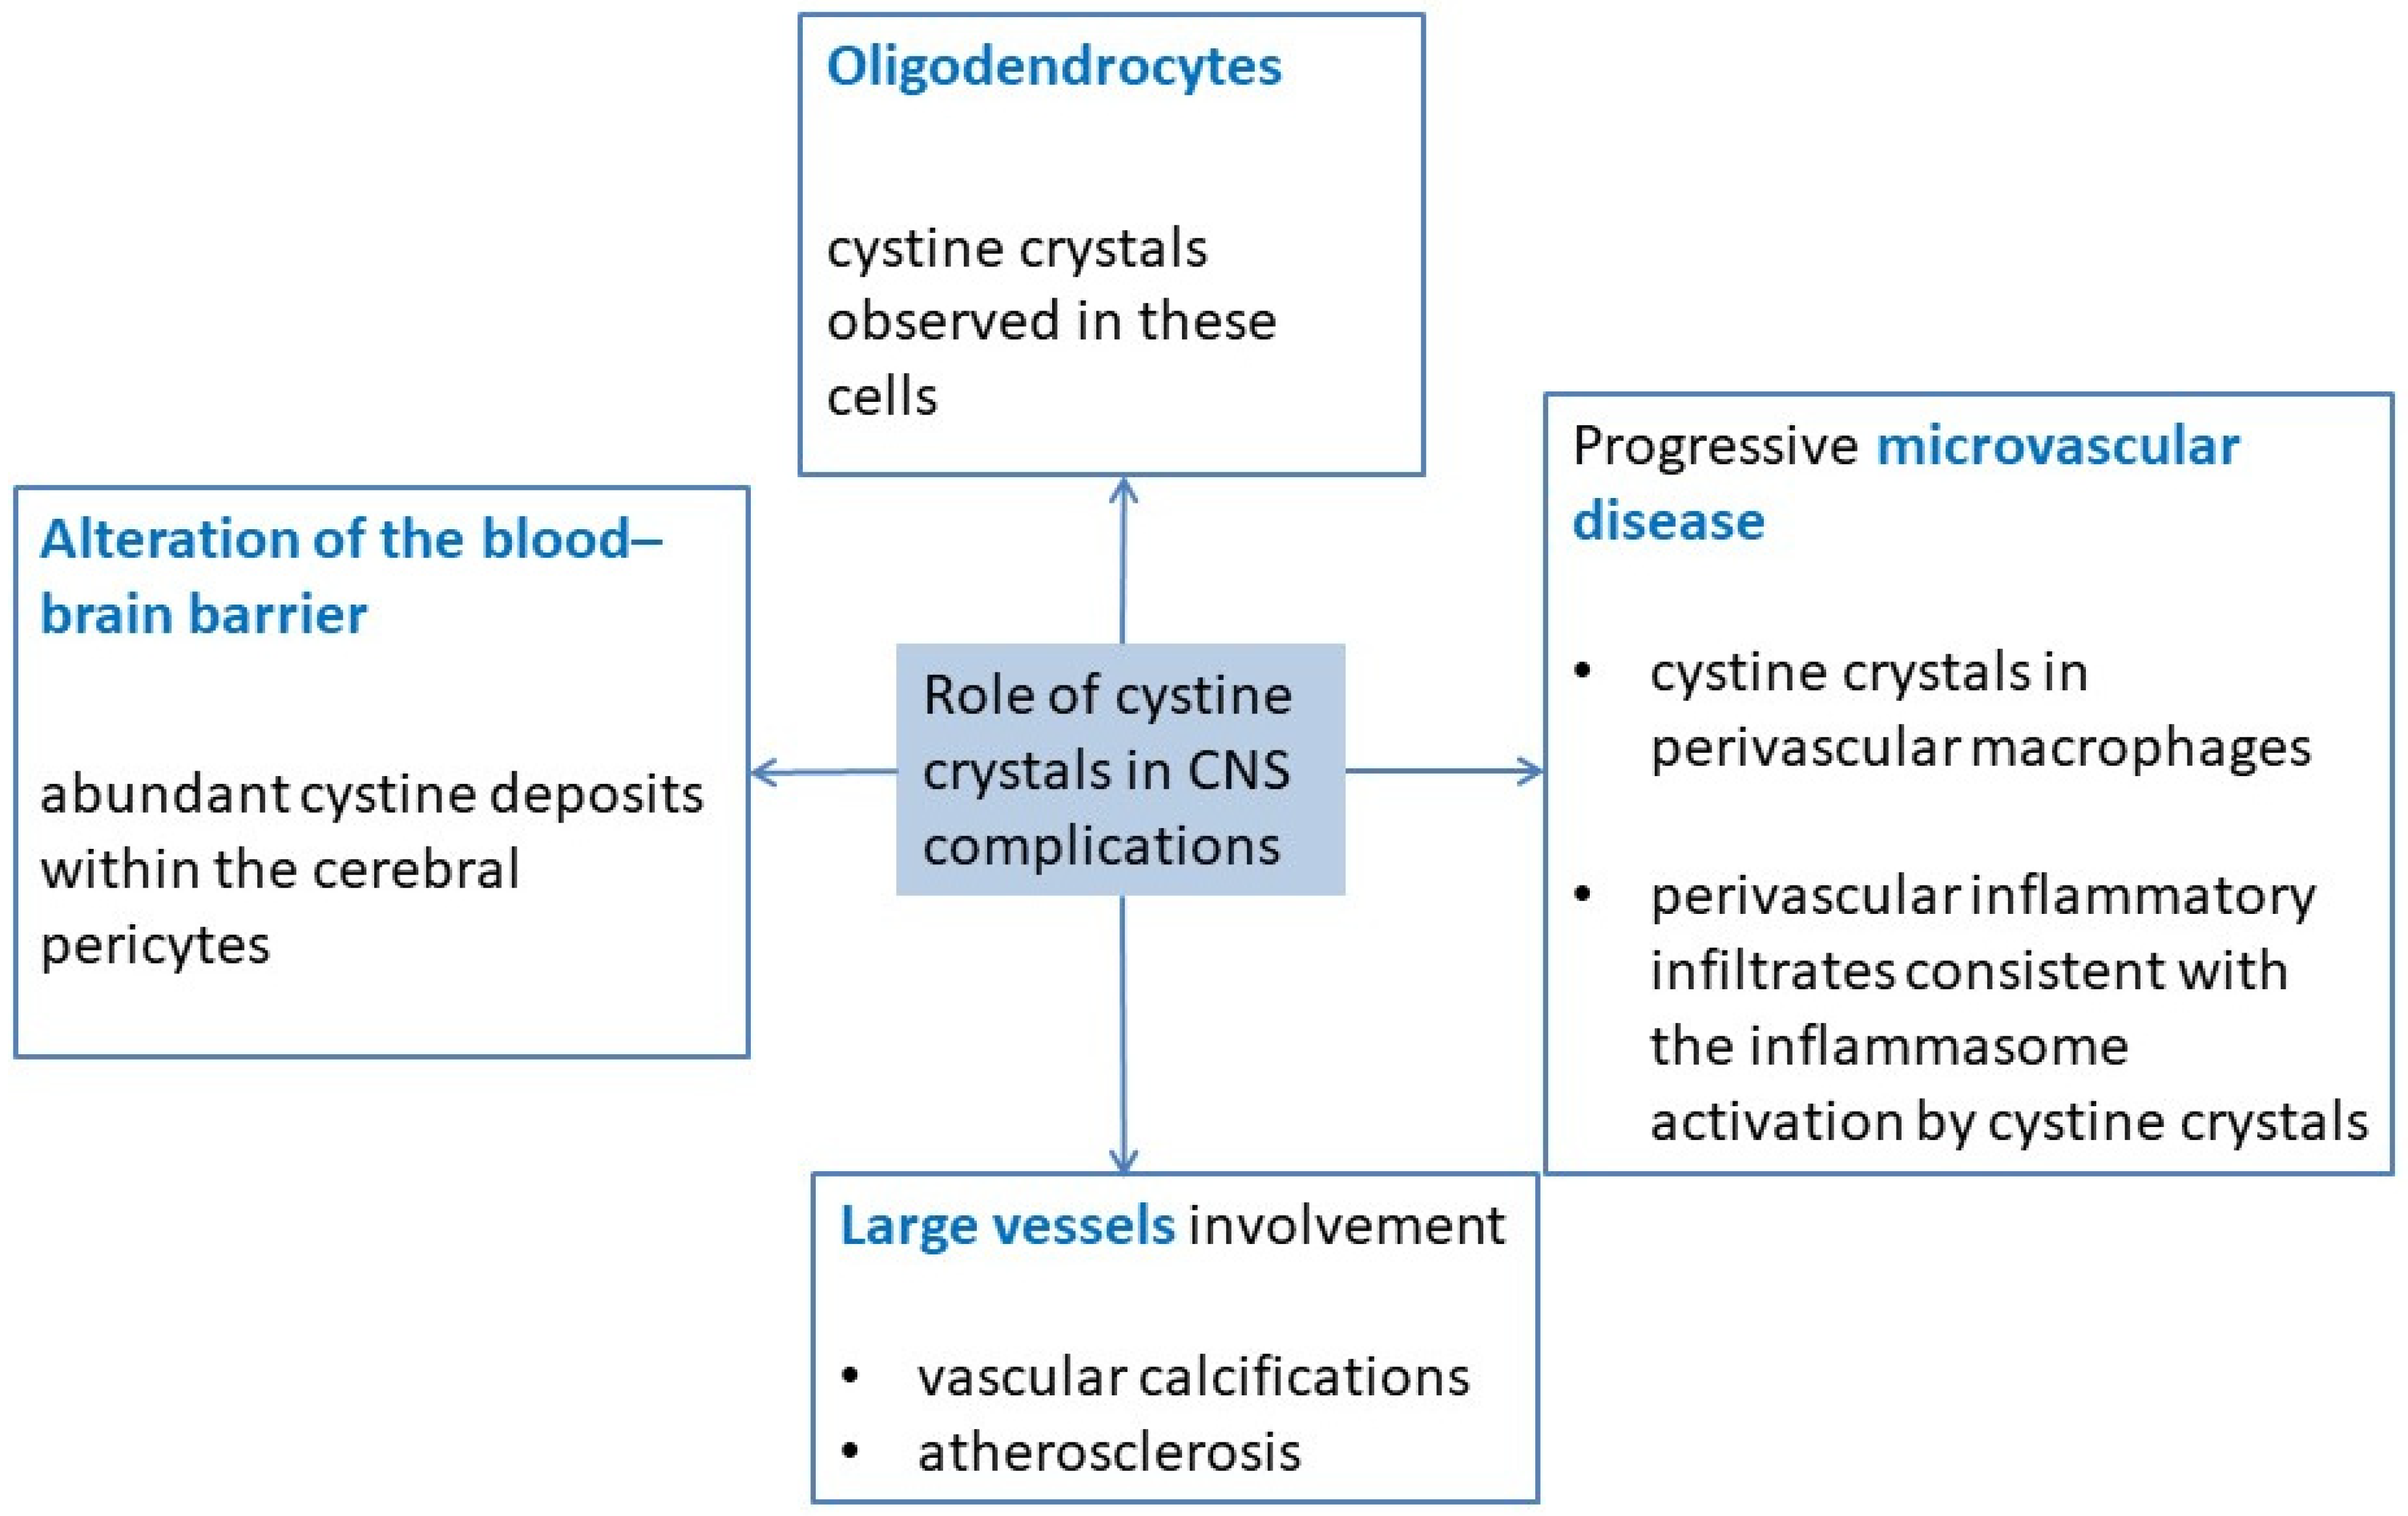

3. Pathophysiology